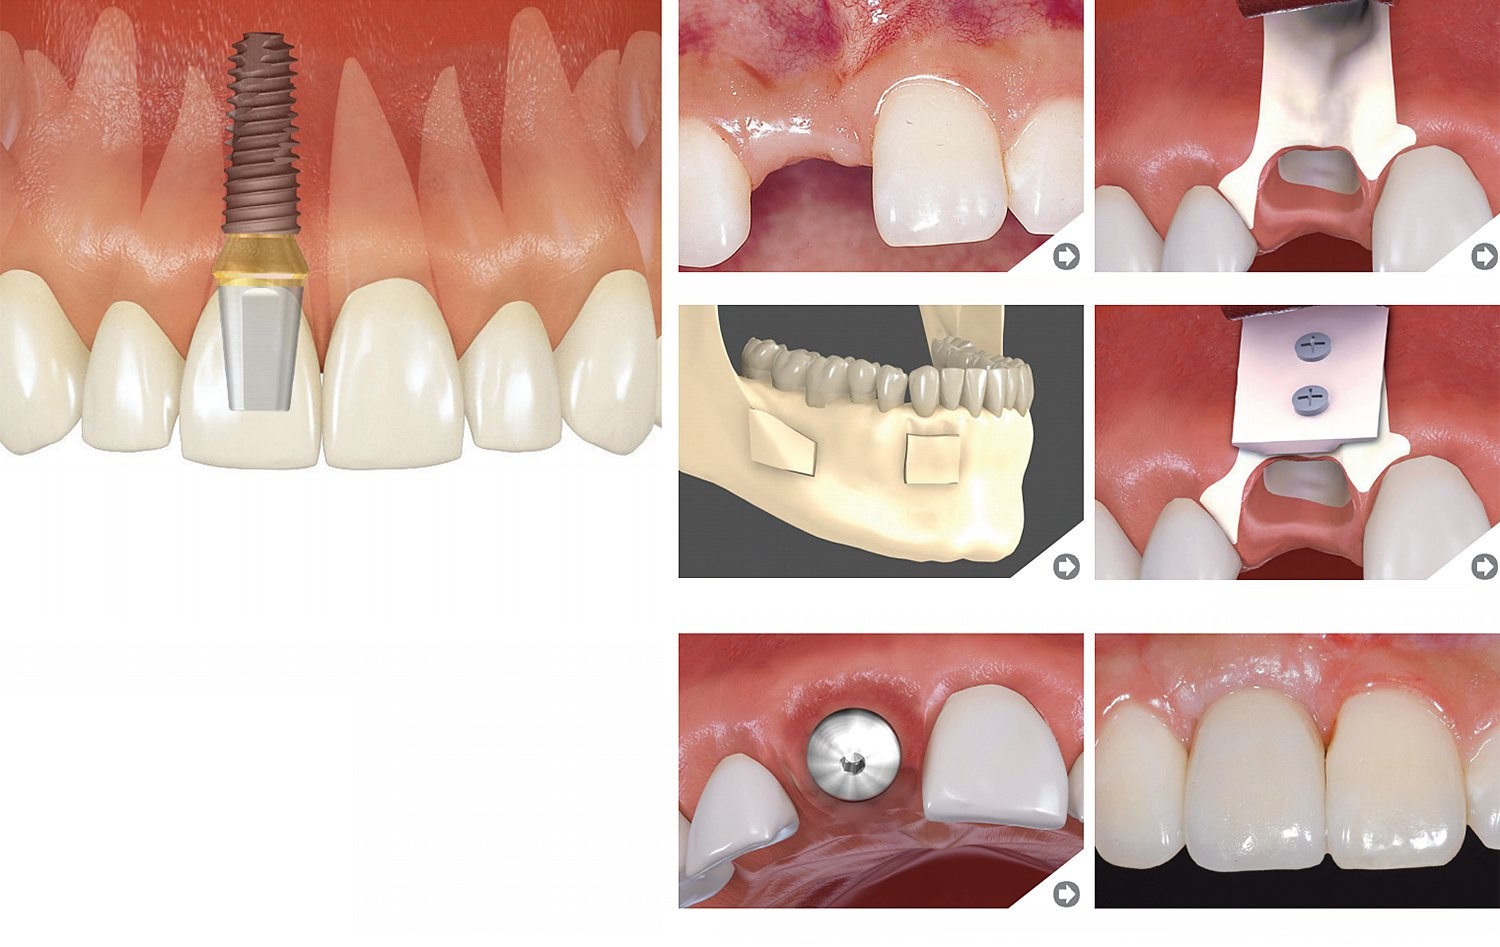

Zobu līnijas pagarināšana (apakšžoklis)

Vadīta kaula pieaudzēšana

Blokveida kaula transplantācija